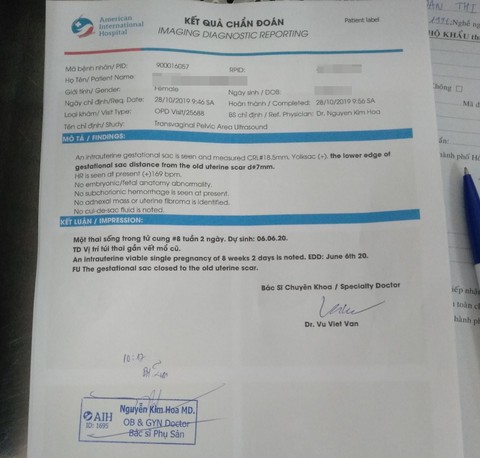

Kết quả siêu âm thai của chị A. tại Bệnh viện Quốc tế Mỹ (AIH) - Ảnh: H.N.

Trình bày với bệnh viện, bác sĩ Hưng cho biết qua thăm hỏi, chị A. xác nhận mình không mang thai. Tuy nhiên, bệnh viện cũng đã siêu âm bụng, khảo sát lòng tử cung và không thấy túi thai vào thời điểm này.

Bà Bành Phương Thảo - giám đốc thẩm mỹ viện Sophie International - cho hay sau gần 1 tháng kể từ ngày hút mỡ bụng tại Bệnh viện thẩm mỹ Emcas, chị A. cùng người thân đến thẩm mỹ viện Sophie International để thông báo mình mang thai 8 tuần, tức khi phẫu thuật hút mỡ chị A. mang thai 4 tuần.

Bà Thảo thông tin thêm sau khi thăm khám, bác sĩ khoa sản Bệnh viện quốc tế Mỹ (AIH) thông tin cho chị A. rằng với thai khoảng 4 tuần là rất khó phát hiện mặc dù đã siêu âm, kiểm tra.